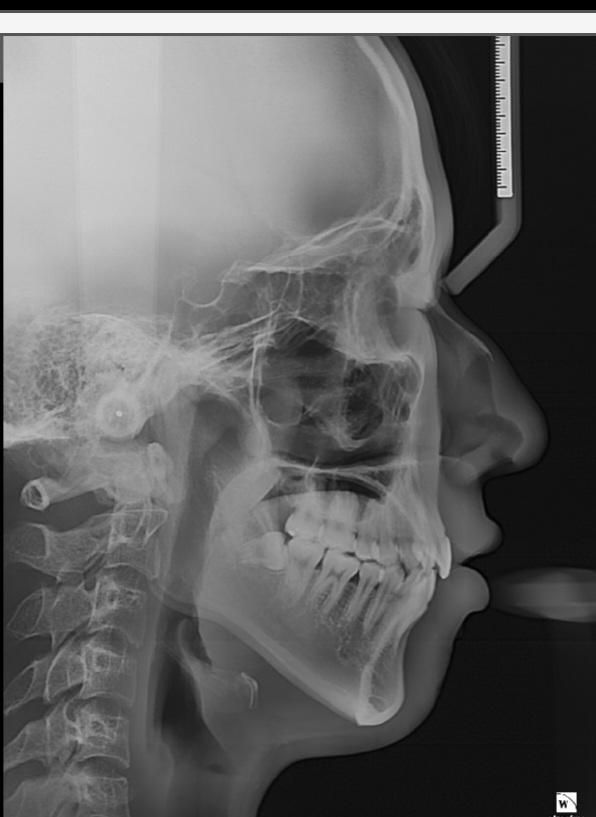

턱뼈가 길어졌는지 확인해주세요..

교정중이고marpè악궁확장장치를 남들보다 훨씬많이 100번넘게 돌렸습니다 20대초남자인데 교정전보다 턱이 길어진것같은데 엑스레이들보고 하악체부길이랑 턱뼈길이 확인해주세요 교정전사진은 턱끝이 경추4번?(몆번인지는 모름)에 도달안했으나 교정후사진은 턱끝이 경추4번?을 넘어갑니다

• 1번 째 사진

현재 사진으로는 악궁확장장치로 인한 영향을 평가할 수 없습니다. 악궁확장장치는 palatine bone을 직접적으로 관여하게 되며 이는 입천장 쪽입니다. 현재 보이는 사진에서 질문자님이 느끼시는 것은 자세 문제 때문입니다. 즉 자세에 따라서 보이는 부분이 달라질 수 있는 것이지 단순히 뼈의 위치로 판단하지 않습니다. 또한 악궁확장장치는 직접적으로 턱뼈가 길어지게 만드는 작용이 아니므로 영향이 적습니다.